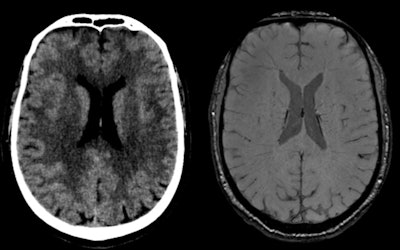

Traumatic brain injury in 64-year-old male skier who had seizures after trauma (broken helmet, Glasgow Coma Scale [GCS] 9/15), psychomotor agitation). CT (left) shows linear hyperdensity adjacent to septum pellucidum. MRI (right) shows susceptibility artifact compatible with hemorrhagic residue in contact with middle part of septum pellucidum on its right lateral surface above the fornix. All figures courtesy of RSNA 2020 and Dr. Mariana Dalaqua.Head and neck injuries account for between 3% and 15% of all injuries. Traumatic brain injury (TBI) is more common in young skiers, children, and adolescents, and brain injuries are the most common severe traumatic injuries associated with skiing, and the injuries with the highest fatality prevalence, Dalaqua and colleagues pointed out in a digital poster.

Disturbances in consciousness or signs of concussion have been reported in 22% to 42% of skiing-related head injuries. Notably, the incidence of head injuries and of potentially serious head injuries has decreased with the widespread use of helmets.

A normal CT is one of the factors that define a brain injury as mild. Initial findings representing diffuse axonal injury can be really subtle and should be further investigated with MRI in cases of high kinetic energy trauma with normal CT and clinico-radiological dissociation, they added.